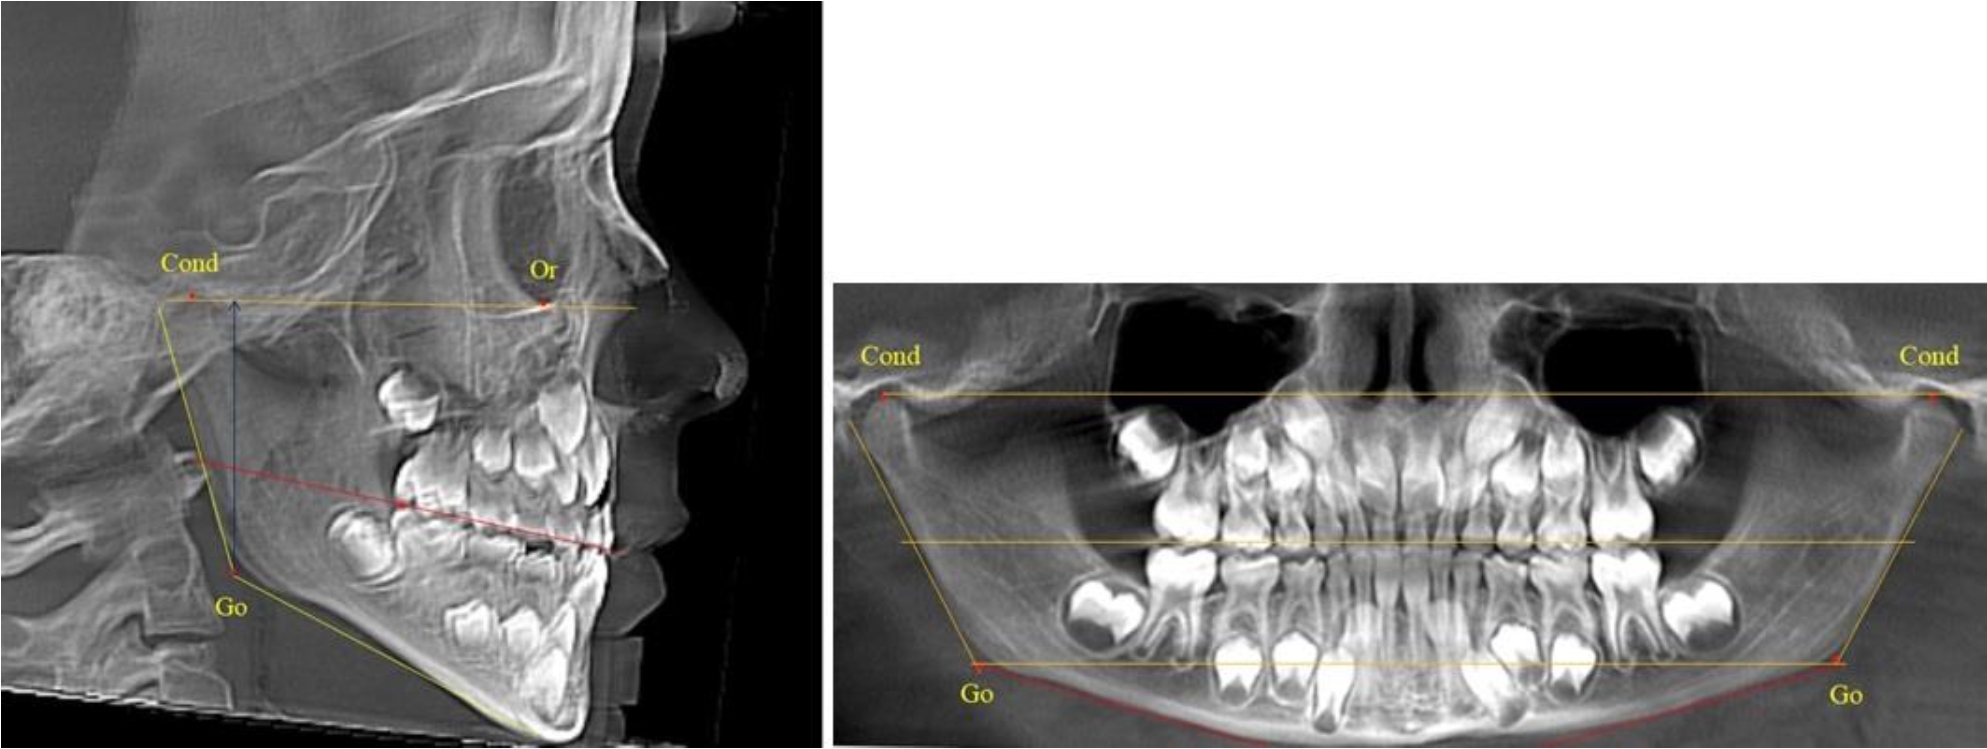

В 5-й группе были проанализированы 14 комплектов рентгенограмм, что составило (13,21 ± 3,29) % от общего числа. На всех рентгенограммах отмечен очередной этап подъема высоты прикуса, обусловленный прорезыванием вторых постоянных моляров. Окклюзионная линия делила ветвь на два отдела (рис. 5).

Рис. 5. ТРГ и ОПТГ пациента после смены молочных зубов и прорезывания вторых постоянных моляров

Высота ветви у детей 5-й группы составляла (62,87 ± 3,62) мм, что было достоверно больше, чем у детей других групп (р ˂ 0,05). При этом высота верхней окклюзионно-суставной части была (40,23 ± 2,01) мм, а нижней – (22,64 ± 1,78) мм. Высота верхней части была вдвое больше нижней, что и определяло особенности соразмерности частей ветви нижней челюсти в анализируемый возрастной период.

Относительные показатели соразмерности частей ветви нижней челюсти показали, что отношение высоты верхней части ветви к нижней в среднем составляло 1,78 ± 0,18. Отношение общей высоты ветви к верхней ее части составляло 1,56 ± 0,12, а отношение общей высоты ветви к нижней ее части было 2,78 ± 0,14, что и определяло особенности соразмерности частей ветви нижней челюсти в анализируемый возрастной период.